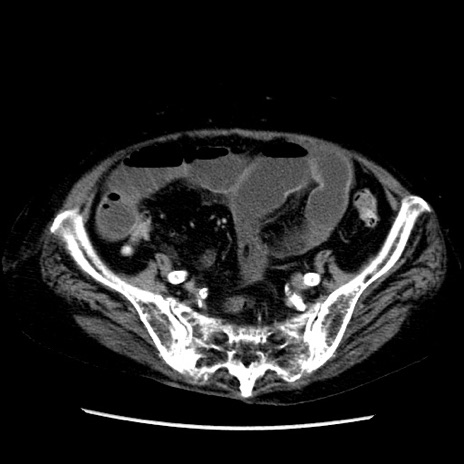

症例14(横断像)

【症例】 90歳代女性

【主訴】 腹痛・嘔吐

【現病歴】今朝から左側腹部痛を認めた。 経過観察していたが、嘔吐を認めたため来院。

【既往歴】 子宮癌術後

【身体所見】 意識清明、BP 127/54mmHg、P 98bpm Sp02 95%(RA)、BT 35.8°C、腹部平坦・軟腸ぜん動音聴取良好、右下腹部圧痛(+) 反跳痛なし

【データ】WBC 9800、CRP 0.46